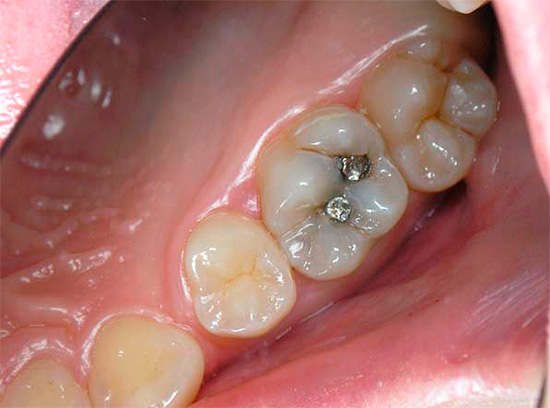

Nella foto - tipico carie delle fessure con manifestazioni esterne minime: